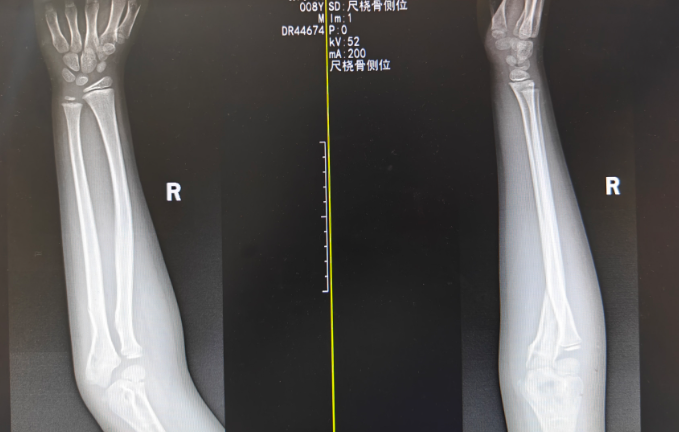

张同学,8岁,在学校上体育课时不慎摔倒,右手肘撞击地面。CT显示:尺骨鹰嘴骨折。多数医师直接建议手术,用钢针进行内固定。理由是,关节内骨折及关节周围骨折,术后能早起功能锻炼防止关节粘连。孩子听说要手术吓得哭了起来,带着焦虑,张同学及家长来到了滨州市中医医院骨伤科(创伤)门诊。

医生通过详细的阅片和体格检查,发现张同学的骨折轻微移位,经过认真考量,为张同学制定了一套“组合拳”式的保守治疗方案,核心在于 “手法复位、弹性固定、中西结合、功能锻炼”。

通过轻柔而精准的中医正骨手法,利用牵拉、挤压、屈伸等动作,使移位的骨折断端“回归原位”。医生“手摸心会,法从手出”。仅用时数分钟,复位完成,X光透视显示对位对线良好。